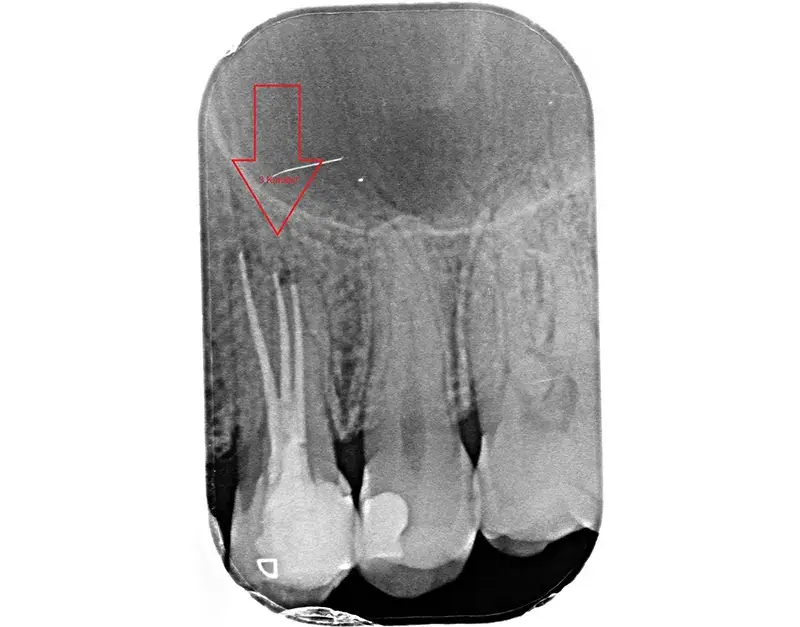

In diesem Fall mussten wir eine mangelhafte Fremdbehandlung korrigieren: Ein im Kanal abgebrochenes Instrument des Vorbehandlers blockierte den Weg und löste eine Entzündung aus. Durch präzises Bypassing konnten wir das Fragment sicher umgehen und bergen, um den Zahn bis zur Wurzelspitze erfolgreich zu retten.

Das Ergebnis dieser Präzision machen wir für Sie sichtbar: Auf dem abschließenden Röntgenbild sticht eine gelungene Wurzelfüllung klar weiß hervor. Sie muss lückenlos bis zur Wurzelspitze reichen und darf keine Lufteinschlüsse aufweisen. Ein entscheidender Punkt dabei: Es müssen zwingend alle Hohlräume behandelt werden – und nicht nur drei von vier Kanälen. Da wir auf diese Behandlungen spezialisiert sind und einen eingetragenen Tätigkeitsschwerpunkt führen, konnten wir bereits viele Zähne retten, die anderswo als verloren galten.

Ein aktuelles Beispiel aus unserer Praxis (siehe Bild) zeigt einen Backenzahn mit fünf statt der üblichen drei Wurzelkanäle. Solche feinen Verästelungen sind eine absolute Rarität und ohne entsprechende Technik kaum zu lokalisieren.